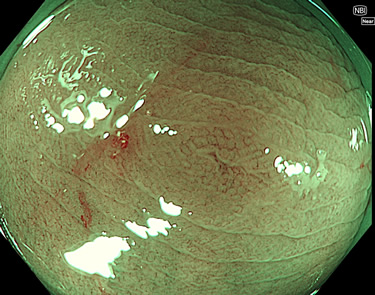

完全に平坦な物をUb、陥凹している物をUcと呼びます。Ubは認識が困難で、Ucはびらん(炎症)と紛らわしいために見落とされやすく、「内視鏡後・大腸癌」の原因になります。

専門的)Uc=De Novo癌? 内視鏡の解像度が低かった時代、このような説もありました。しかし今日の高精度内視鏡では良性の微小なUc型腺腫(APC遺伝子異常の腺腫)が日常的に見つかります。Ucこそが多段階発癌(Adenoma-Carcinoma Sequence)のMain Routeです。